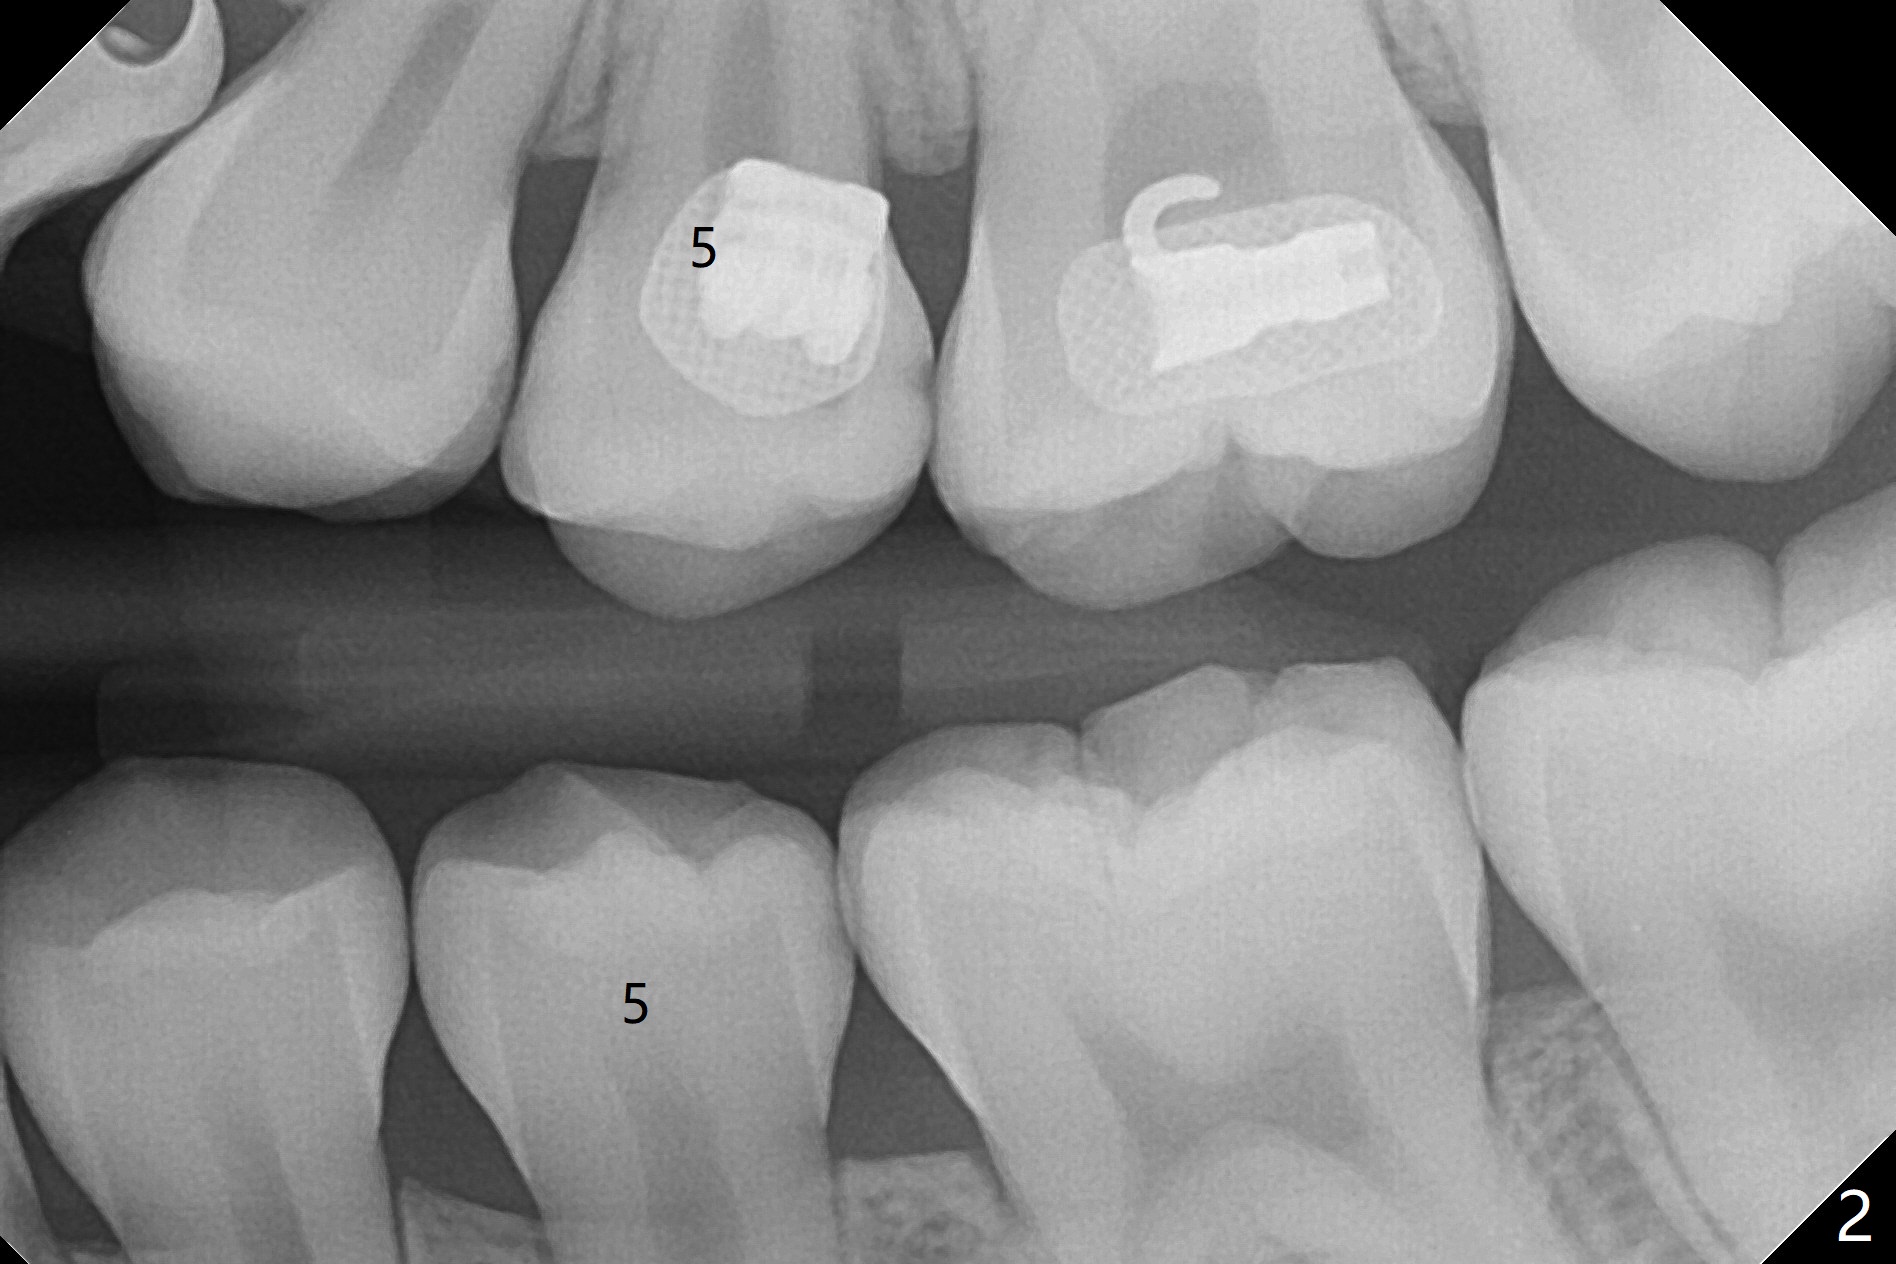

A 14-year-old woman with crowding returns to clinic for extraction of the 1st bicuspids. Orthodontic treatment has started partially. Because of severe caries at UR5 (Fig.1 *), BWs and PA are taken, which reveal DO incipient caries at UL, LL5 (Fig.2) and large PARL at UR5 (Fig.3 *). Upon receiving a revised treatment plan, four of 2nd bicuspids are extracted. The large PARL is confirmed intraop. Examination of the extracted teeth shows mesial caries at UL5, which is not detected by X-ray (Fig.4 <). By comparison, DL caries of UL5 is more severe (Fig.5). Check the neighboring teeth for caries when the patient returns for recall. The pulpal exposure of UR5 is large (Fig.6). So is the pulpal chamber (Fig.7). The large canal (Fig.7) in fact consists of 2 ones (Fig.11 red arrows) with a separation in between (*). The DL caries at LL5 is at the stage of decalcification (Fig.8), not visible in X-ray (Fig.12, as compared to Fig.7 >).